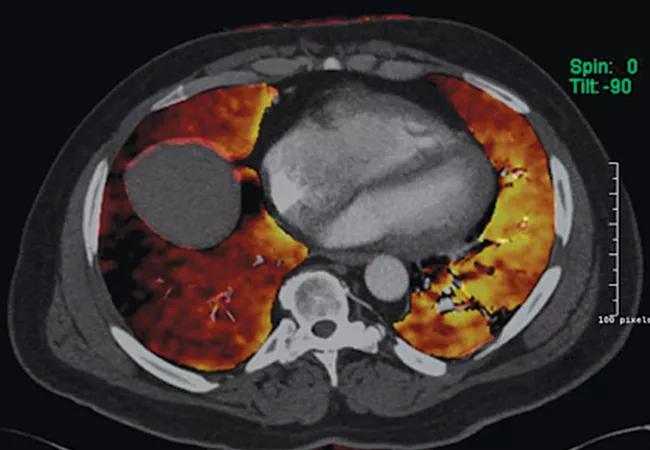

Radiographic changes associated with CTEPH are distinct from the intraluminal filling defects seen with acute thromboembolism, since chronic thrombi tend to become organized and eccentric. On imaging, one may see features of rapid luminal narrowing or eccentric filling defects rather than the conventional central filling defects of acute pulmonary embolism. These changes are often overlooked by radiologists who are not specifically looking for CTEPH. For this reason, the sensitivity and specificity of identifying chronic thromboembolic disease using radionuclide ventilation-perfusion lung scanning is superior to that of CT angiography.

All patients with suspected PAH should undergo a ventilation-perfusion scan. In patients with ventilation-perfusion mismatch on radionuclide scanning, pulmonary angiography can fulfill multiple goals of measuring pulmonary arterial pressures, identifying the extent and location of chronic thromboemboli and can determine whether surgical thromboendarterectomy is feasible.